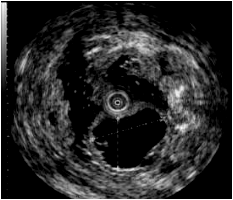

五、超声内镜诊疗技术

超声内镜(EUS)是将内镜和超声相结合的消化道检查技术,将微型高频超声探头安置在内镜前端,当内镜插入消化道后,在内镜直接观察消化道黏膜病变的同时,可利用内镜下的超声探头行实时超声扫描,可以获得胃肠道的层次结构的组织学特征及周围胆胰等邻近脏器的超声图像,从而进行特定肿瘤的诊断和治疗。

内镜下可见降部黏膜下肿物 超声内镜下可见黏膜下低回声囊肿